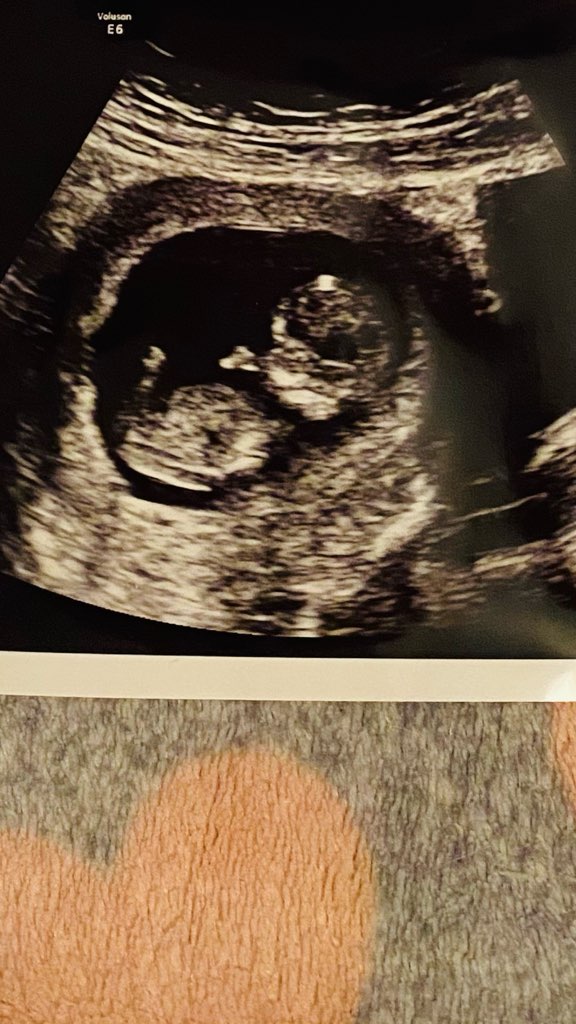

Dziewczyny wczorajsza wizyta bardzo udana ! I wiecie co miesiące mi się pomyliły bo przewidywana data porodu 21 marzec 😅😅 ale napisze Wam ze fasolka tak tańczyła raz to na plecki raz na brzuszku ze to było takie słodkie i wzruszające i te stopki jak zobaczyłam to ajj 🥺🥺 tyle stresu niepotrzebnego od dziś nie czytam żadnych negatywnych wiadomości bo ca ma być to i tak się wydarzy trzymam kciuki za Was wszystkie ❤️❤️❤️❤️

Załączniki

• IMG_5022.jpg

IMG_5022.jpg

116,8 KB · Wyświetleń: 110